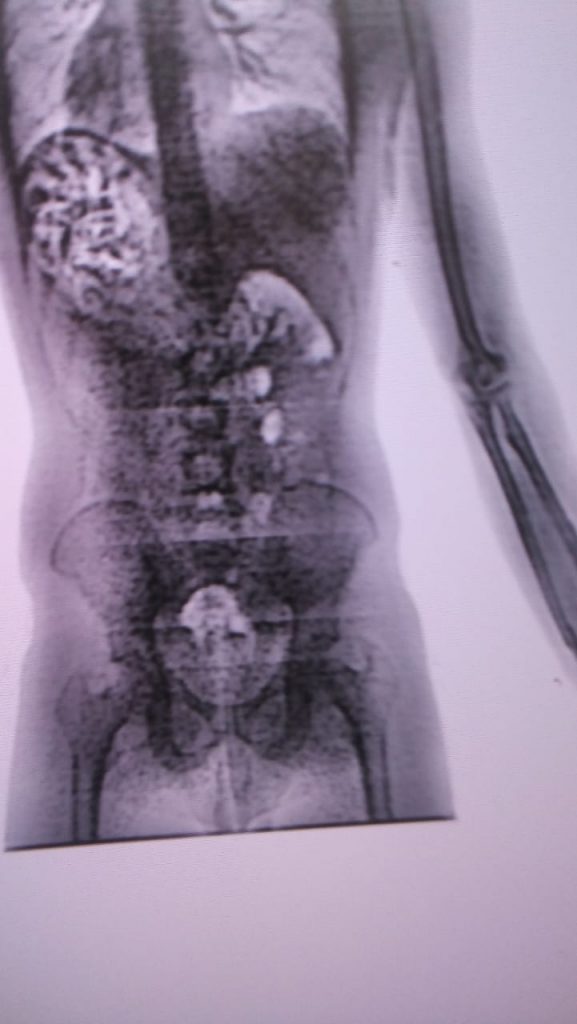

Os chamados “body scan” flagram visitantes que tentam entrar com drogas e objetos proibidos nos presídios

Dois homens foram presos ao tentarem entrar no Presídio Regional Juiz Manoel Barbosa de Souza, em Tobias Barreto. Os irmãos estavam com quase um quilo de drogas escondido no estômago. O fato aconteceu nesta terça-feira, 5, a droga foi flagrada pelos “body scan”, um escâner corporal que identifica drogas e outros objetos no momento em que visitantes entram nos presídios.

No momento em que eles passaram pelo body scanner, foi detectada uma anormalidade nas imagens. Ao serem questionados pelo diretor José Raimundo, os dois confessaram a que estavam com o entorpecente e retiraram a droga.